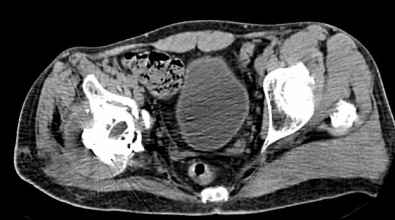

Мужчина, 45 лет. 6 мес. назад перенес тотальное эндопротезирование правого тазобедренного сустава по поводу ложного сустава шейки бедра.

Характер реконструкции вертлужной впадины не известен. Через 3 мес. после операции отметил щелчки и хруст при движениях в области эндопротеза. В анамнезе туберкулез легких. Сейчас, по заключению фтизиатра, в легких активного процесса нет. Местного воспаления нет.Предполагается нестабильность чашки в связи с бактериальным воспалением. Планируется удаление чашки и цемента, пластика дна измельченными аутотрансплантами и гидроксилапатитной керамикой, затем кольцо Мюллер, цементная чашка.

Смущает и ножка - зона просветления вокруг мантии. Предложения по тактике?

прямо скажем, очень загадочная конструкция с проволокой и винтами. :) На основании чего Вы подозреваете септическую нестабильность? Каковы результаты анализов? Согласен с доктором - нужно сделать пункцию. Есть ли снимки до и сразу после операции? Знаете ли Вы диаметр головки,какой будет внутренний диаметр Вашей чашки? Известно ли, чей протез? Может есть смысл найти автора работы и узнать о подробностях установки протеза?